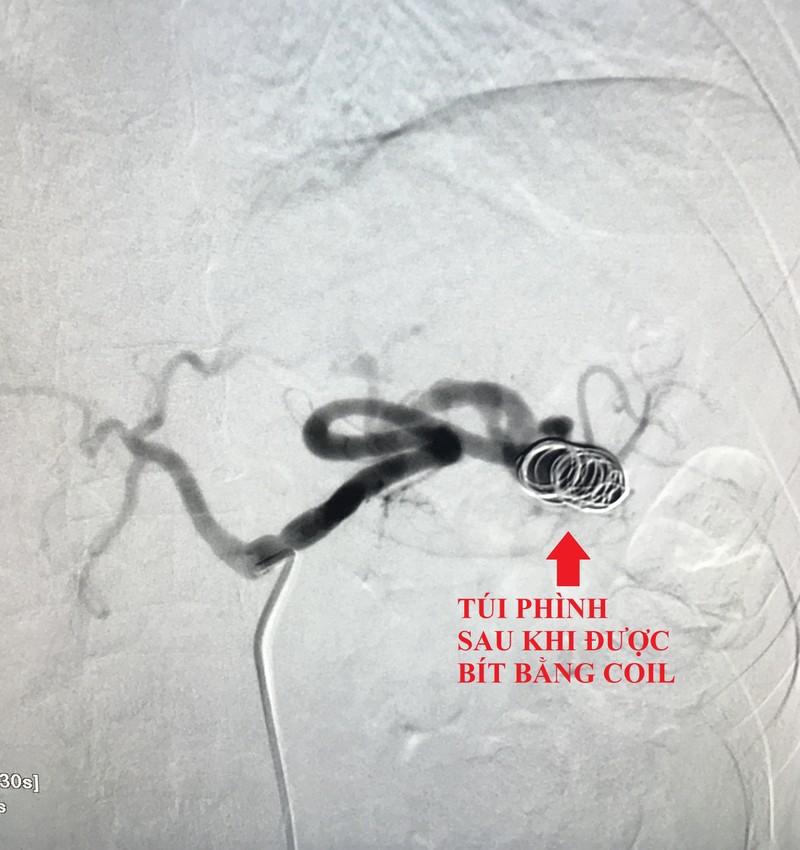

Theo đó, các bác sĩ mở một lỗ nhỏ ở động mạch đùi, qua đó luồn ống thông vô đến lỗ động mạch lách, sau đó đến vị trí túi phình và thả 3 coil (vòng xoắn kim loại) bít hoàn toàn túi phình. Bệnh nhân hết đau tức vùng bụng và được xuất viện sau 2 ngày.

Túi phình động mạch lách sau khi được bít bằng coil. Ảnh: BVCC